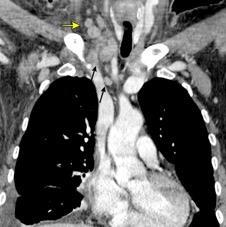

Masa axilar izquierda y derrame pleural derecho. Implantes pleurales, paraespinales . Ganglios en mamaria interna. Linfoma B difuso

Jaffe ES. Diagnosis and Classification of Lymphoma: Impact of Technical Advances.

2005. Masa pulmonar.